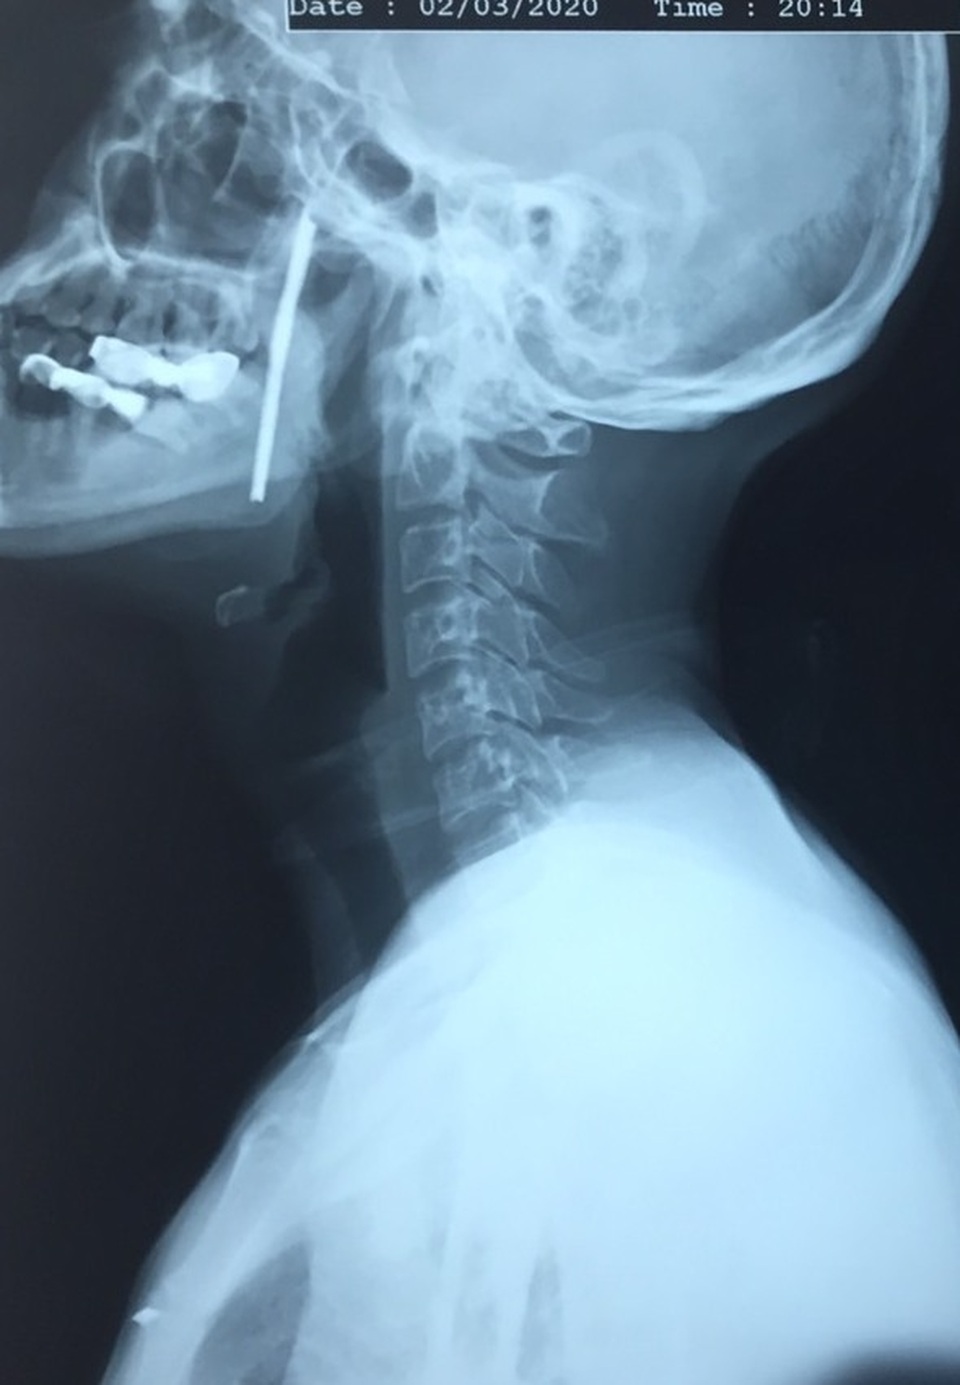

(Dân trí) - Khi được đưa tới Bệnh viện Việt Đức cấp cứu, thanh kim loại dài khoảng 10cm vẫn cắm sâu trong cổ bệnh nhân. Chẩn đoán cho thấy thanh sắt dài xiên từ hầu họng vào trong miệng bệnh nhân.

TS Vũ Ngọc Tú, Trung tâm Phẫu thuật Tim mạch và Lồng ngực, Bệnh viện Hữu nghị Việt Đức cho biết, trên cơ sở phân tích kĩ càng cơ chế ngoại lực, các dấu hiệu lâm sàng thực tế và các xét nghiệm hình ảnh, người bệnh được chẩn đoán vết thương phức tạp vùng cổ, do dị vật kim loại dài, xiên từ hầu họng vào trong miệng.

Điều may mắn cho bệnh nhân, dù thanh sắt xuyên từ vùng hầu họng và miệng, nhưng nó chưa trực tiếp gây tổn thương các thành phần này. Tuy nhiên, việc nằm sát các cơ quan hệ trọng của cơ thể khiến các bác sĩ phải tính toán làm sao lấy dị vật ra nhưng đảm bảo tính mạng người bệnh và xa hơn nữa là giữ được chức năng cơ thể.

Bệnh nhân được đẩy vào phòng mổ cấp cứu, với sự kết hợp hết sức chặt chẽ và chuyên nghiệp của ê kíp phẫu thuật gồm các phẫu thuật viên lồng ngực - mạch máu và phẫu thuật hàm mặt, dị vật kim loại được bộc lộ hết sức rõ ràng, cách ly đảm bảo an toàn với tất cả các thành phần xung quanh, đặc biệt là các mạch máu nuôi não.

Sau quãng thời gian cân não, cuối cùng dị vật kim loại đã được lấy ra, đảm bảo an toàn tuyệt đối cho người bệnh. Đây là thanh kim loại dài hơn 10cm, rất sắc nhọn.